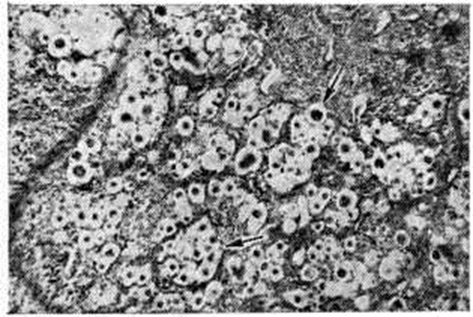

Диагноз криптококкоза при цитологический исследовании мокроты и гистологический исследовании биоптатов ткани лёгкого становится убедительным после постановки PAS-реакции (смотри полный свод знаний ШИК-реакция) и применения других методик, позволяющих выявить располагающуюся вокруг грибка желатинозную капсулу, богатую глюкозаминогликанами. Этиотропная терапия криптококкоза лёгких предполагает использование амфотерицина В под контролем функции почек. Прогноз при локализованном лёгочном криптококкозе благоприятный. Гематогенная диссеминация процесса сопровождается развитием энцефаломиеломенингита с плохим прогнозом. Известны рецидивы лёгочного криптококкоза. Североамериканский бластомикоз с локализацией первичного патологический процесса в лёгких развивается в результате аэрогенного заражения грибком Blastomyces dermatitidis (смотри полный свод знаний Бластомикозы) и является редкой формой заболевания. Очаги поражения при североамериканском бластомикозе имеют сходство с таковыми при раке или туберкулёзе, так как подвергаются творожистому некрозу или гнойному расплавлению. При гистологический исследовании обнаруживают очаги некроза с разрастанием грануляционной ткани в их окружности, которая содержит гигантские клетки. PAS реакция выявляет Blastomyces dermatitidis среди клеток инфильтрата или в гигантских клетках (рисунок 2). Лёгочная форма североамериканского бластомикоза начинается незаметно и в ранний период может протекать под маской острого респираторного заболевания с небольшим повышением температуры тела, незначительным кашлем, который обычно сопровождается отделением небольшого количества слизистой или слизисто-гнойной мокроты, у некоторых больных наблюдаются боли в грудной клетке. В дальнейшем состояние больных прогрессивно ухудшается, температура тела достигает высоких цифр, сопровождается ночными потами, ознобами, постепенно развиваются слабость, анорексия, истощение. Кашель становится почти постоянным и мучительным, мокрота — обильной и гнойной, часто с прожилками крови. Физикальное исследование выявляет признаки очаговых изменений в лёгких (локальное притупление перкуторного звука, разнокалиберные хрипы). Иногда очаговые лёгочные поражения остаются изолированными в течение всего своего развития, в некоторых случаях принимают распространённый (диссеминированный) характер. Длительное и прогрессирующее течение болезни может сопровождаться поражением тел позвонков и компрессией спинного мозга. В крови отмечается гипохромная анемия, лейкоцитоз, нейтрофилез, ускорение РОЭ. При рентгенологическое исследовании в начальной стадии болезни обнаруживают увеличение медиастинальных лимфатических, узлов без заметных изменений в ткани лёгкого, в дальнейшем выявляются плотные тени с неправильными контурами, расположенные чаще в области корней лёгких, симулирующие новообразование. Образование каверн нехарактерно, однако иногда они встречаются у лиц пожилого возраста. Лечение осуществляется с помощью амфотерицина В. Прогноз серьёзный, в случае диссеминированного процесса плохой. Паракокцидиоидоз вызывается грибком Paracoccidioides brasiliensis (смотри полный свод знаний Паракокцидиоидоз) и в 80% случаев протекает с первичным поражением лёгких. Паракокцидиоидоз характеризуется хронический прогрессирующим течением и гранулематозным процессом в лёгочной ткани и нередко гнойным воспалением. Общее состояние больных постепенно ухудшается, развиваются астения, анорексия, гектическая лихорадка, ночные поты. Кардинальным симптомом заболевания является кашель со слизистой мокротой, которая со временем становится гнойной с прожилками крови. Как правило, лёгочные поражения сопровождаются повреждением других внутренних органов: желудка, кишечника, печени и так далее, в которых развиваются гранулемы или абсцессы. Рентгенологические исследование выявляет расширение корней лёгких и признаки, сходные с симптомами инфильтративно-кавернозного туберкулёза лёгких (смотри полный свод знаний Туберкулёз органов дыхания). Нередко имеет место сочетание туберкулёза и паракокцидиоидоза. Установление диагноза заболевания возможно только при обнаружении почкующихся дрожжевых клеток в мокроте, соскобах с поверхности грануляций, в выделениях из свищевых ходов. При лечении используется амфотерицин В. Прогноз при своевременной диагностике и терапии благоприятный. Геотрихоз. Возбудитель — грибок рода Geotrichum. Наиболее частой клинические, формой первичного геотрихоза органов дыхания является бронхит. Симптомы интоксикации не выражены. Характерен мучительный кашель, сопровождающийся выделением слизистой или желеобразной мокроты, в которой можно видеть серые комочки мицелия грибка или прожилки крови. При физикальном обследовании больного выявляются грубые свистящие хрипы над областью поражения, преимущественно в базальных сегментах лёгких. Рентгенологические картина характеризуется усилением бронхиального рисунка и наличием нежных пятен затемнения, в основном в нижних долях лёгких. Геотрихоз с преимущественным поражением ткани лёгкого обычно является вторичным. Очаги поражения локализуются в верхних отделах лёгких и могут захватывать целую долю. При гистологический исследовании ткани лёгкого характерных морфологический особенностей, кроме обнаружения грибка, не выявляется. При наличии тонкостенных каверн, являющихся следствием туберкулёзного процесса, осложнившегося геотрихозом, на их стенках находят разросшиеся мицелиальные формы грибка. Заболевание протекает с нерегулярным повышением температуры, одышкой и тахипноэ, тахикардией и явлениями интоксикации. Характерен кашель с выделением светлой мокроты, иногда с прожилками крови. Кровохарканье наблюдается редко. При физикальном исследовании определяется притупление перкуторного звука над очагами поражения, выслушиваются мелкопузырчатые и среднепузырчатые хрипы. Рентгенологически обнаруживают тяжистость лёгочного рисунка, гладко-очерченные плотные тени, в которых могут быть тонкостенные каверны. В крови сегментоядерный лейкоцитоз, ускорение РОЭ. Этиотропное лечение геотрихоза включает амфотерицин В, а также амфоглюкамин в виде ингаляций. Прогноз при своевременном лечении благоприятный. Гистоплазмоз лёгких вызывается Histoplasma capsulatum Darling (смотри полный свод знаний Гистоплазмоз). Первичный гистоплазмоз лёгких в большинстве случаев протекает бессимптомно, но иногда может симулировать грипп и другие острые респираторные заболевания. Вторичный гистоплазмоз лёгких протекает в виде хронический процесса, который периодически обостряется, а иногда переходит в диссеминированный системный гистоплазмоз. Кокцидиоидоз лёгких, вызываемый грибком Coccidioides immitis (смотри полный свод знаний Кокцидиоидоз), чаще встречается в форме первичного и обычно протекает доброкачественно. Морфологически изменения в лёгких при кокцидиоидозе разнообразны: очаги уплотнения лёгочной ткани, обширные студенистые очаги или очаги нагноения, некротический язвенный бронхит, гранулематозные поражения без некроза и очаги обызвествления с некрозом в центре. Реже встречающийся вторичный кокцидиоидоз лёгких имеет сходство с туберкулёзом. При этом наблюдаются казеозная пневмония, абсцессы, в которых обнаруживают сферулы грибка (рисунок 3). Клинические, проявления болезни могут ограничиваться признаками острого респираторного заболевания. Спустя несколько недель наступает выздоровление. У 4—5% инфицированных лиц кокцидиоидоз с поражением лёгких протекает в тяжёлой форме, сопровождается высокой температурой, одышкой, кашлем с гнойной мокротой, иногда кровохарканьем. Наблюдаются резкие колебания температуры в течение суток, сопровождающиеся ознобами и потами. Больные жалуются на головную боль, боль в мышцах, пояснично-крестцовой области. В последующем развиваются анорексия, астения, снижается вес (масса) тела больных. Над лёгкими выслушиваются сухие и влажные хрипы, иногда — шум трения плевры. В течении болезни отмечаются длительные периоды ремиссии. Иногда наблюдается диссеминация возбудителя инфекции и развитие грибкового сепсиса с образованием множественных абсцедирующих инфильтратов в различных органах и тканях.

При рентгенологическое исследовании находят расширение и уплотнение корней лёгких, единичные или множественные инфильтраты различной плотности и величины, расположенные обычно в нижних и средней долях лёгких. На месте распадающихся инфильтратов образуются тонкостенные каверны. Для лечения кокцидиоидомикоза применяют амфотерицин В. При первичных формах поражения лёгких исход благоприятный. Прогноз при генерализованных формах болезни плохой. Аспергиллез лёгких— наиболее частая форма висцерального аспергиллёза. Заражение происходит при вдыхании спор грибка рода Aspergillus (смотри полный свод знаний Аспергиллез). Первичный аспергиллез лёгких встречается редко, вторичный развивается у ослабленных лиц на фоне тяжёлых болезней (туберкулёз и рак лёгкого бронхоэктазы и так далее), а также при длительном лечении антибиотиками, глюкокортикостероидами, цитостатиками. Первичный острый бронхолёгочный аспергиллез может протекать по типу тяжёлой пневмонии, бронхита. На лёгочную ткань процесс переходит вследствие радиарного роста концевых отделов мицелия грибка, который проникает через стенки бронхов, Межальвеолярные перегородки, стенки капилляров, артерий и вен (рисунок 4, я, б). В участках секвестрации аспергиллёзной пневмонии иногда формируется аспергиллома лёгкого, которая представляет собой шарообразное разрастание грибка (Fungus ball), с последующим образованием полости. Внедрение мицелия в стенку полости, сопровождающееся фиброзно-гнойной экссудацией, обозначается как инвазивная аспергиллома. В начале болезни наблюдают сухой мучительный кашель, одышку, озноб и лихорадку. В дальнейшем присоединяется кровохарканье, нарастает слабость, астения, анорексия, над поверхностью лёгких выслушиваются множественные разнокалиберные хрипы. Рентгенологически определяются участки инфильтрации лёгочной ткани, склонные к распаду с образованием полостей, увеличиваются бронхолёгочные (корневые) лимфатических узлы. При отсутствии лечения заболевание принимает хронический течение с ремиссиями и обострениями. Постепенно увеличивается количество мокроты, которая становится кровянисто-гнойной. Периоды обострения сопровождаются гектической лихорадкой, ознобом, ночными потами, снижением веса тела больного. Перкуторно определяют коробочный звук и его притупление при субплевральном расположении очага поражения, аускультативно — сухие и мелкопузырчатые влажные хрипы. При вторичном аспергиллёзе лёгких довольно часто (в 70% случаев) развивается аспергиллома, которая формируется в санированных туберкулёзных кавернах, бронхоэктазах, полостях, образовавшихся после абсцессов, гангрены или инфарктов лёгких, вскрывшейся эхинококковой кисты. Аспергиллома представляет собой полость, сообщающуюся с просветом бронха и содержащую плотные сплетения нитей грибка в виде тяжей серого цвета и наложений на стенках полости. Изнутри полость выстлана эпителием и грануляционной тканью, легко кровоточащей при перемещении её содержимого. Заболевание проявляется постепенным нарастанием слабости, понижением аппетита, неправильной лихорадкой, ознобом и повышенной потливостью. Характерный признак — приступообразный кашель с отделением обильной мокроты без запаха, содержащей зеленовато-серые хлопья (скопления мицелия грибка) и прожилки крови. Могут возникать повторное кровохарканье, иногда значительное, боли в груди, одышка. При отсутствии бронхолёгочного дренажа характерные симптомы не наблюдаются. Физикальное обследование больного выявляет признаки имеющейся в лёгком полости. Рентгенологически вначале определяется утолщение стенок полости, затем секвестроподобное затемнение, окружённое серповидным просветлением («нимб», «ореол», «полумесяц» и тому подобное), которое может смещаться при перемещении тела больного («симптом погремушки») или всплывать при заполнении полости рентгеноконтрастным веществом («симптом поплавка»). Аспергиллез лёгких может протекать с поражением плевры. Иногда разросшийся мицелий грибка выполняет плевральную полость, в других случаях развивается выпотной плеврит. При постоянном вдыхании спор грибка может наблюдаться аспергиллезный аллергический альвеолит (смотри полный свод знаний Пневмония). Для лечения аспергиллёза лёгких применяют амфотерицин В, препараты йода в постепенно возрастающих дозах, нистатин, леворин в виде ингаляций; в ряде случаев используют оперативные методы лечения. Прогноз при своевременном лечении аспергиллёзного пневмомикоза благоприятный. Пенициллиоз лёгких — основная форма этого редкого заболевания, вызываемого различными видами грибков рода Penicillium и протекающего в виде вторичного процесса. Патологический процесс локализуется чаще в бронхах, где развивается картина гнойно-некротического бронхита. Заболевание характеризуется длительно существующим кашлем со слизисто-гнойной, иногда кровянистой мокротой, субфебрильной температурой, похуданием. Рентгенологически выявляются фиброзные узлы в области корней лёгких, реже — инфильтраты с абсцедированием и образованием каверн. Для лечения применяют амфотерицин В, нистатин, леворин в виде ингаляций натриевой соли; в ряде случаев применяют оперативное лечение (смотри полный свод знаний Пенициллиоз). Прогноз серьёзный. Мукороз. Возбудителями заболевания являются различные виды грибков из семейства Mucoracea (смотри полный свод знаний Плесневые микозы). Мукороз лёгких развивается в виде эндогенной инфекции без специфической симптоматики. Морфологически характеризуется поражением бронхов, лёгочной ткани и сосудов. В бронхах чаще наблюдаются язвенные изменения со слабо выраженной воспалительной реакцией. Для мукорозной пневмонии характерны некрозы, окружённые небольшим скоплением лейкоцитов, плазматических клеток и эозинофилов. Типично раннее прорастание мицелия грибка в стенки сосудов, что способствует тромбообразованию. Возбудителей обнаруживают в зоне некроза и в гигантских клетках. Клинически наблюдают очаговую пневмонию, плеврит, инфаркты лёгкого, проявляющиеся кашлем со скудной слизисто-гнойной мокротой, кровохарканьем, лихорадкой, сегментоядерным лейкоцитозом. Рентгенологически выявляют пятнистые тени различного размера и плотности, нередко — каверны. Возможна генерализация процесса с формированием абсцессов в надпочечниках, головном мозге, сердце, что приводит к быстрой гибели больных. Лечение больных мукорозом предусматривает применение амфотерицина В. Адиаспоромикоз — редкая форма пневмомикоза, вызываемая Emmonsia crescens и реже Etmonsia parva (Haplosporangium). Единичные случаи болезни описаны в Швеции, Норвегии, Финляндии, Франции, ЧССР и СССР. Различают две формы поражения лёгких при адиаспоромикозе: с одиночными гранулемами или с милиарной диссеминацией, вероятно, в результате гематогенной диссеминации и скопления большого числа адиаспор, диаметр которых может достигать 300—700 микрометров. Клиническая картина болезни изучена недостаточно. Споротрихоз лёгких, или споротрихозный пневмомикоз,— редкая форма висцерального споротрихоза (смотри полный свод знаний), вызываемого грибком Sporotrichium schenckii. Наблюдается преимущественно у мужчин в возрасте 20—40 лет, занимающихся сельско-хозяйственным трудом. Споротрихозный Пневмомикозы может носить первичный или вторичный характер и протекать как с преимущественным поражением трахеобронхиальных лимфатических, узлов или лёгочной ткани, так и с их сочетанным поражением. В лёгких развивается гранулематозное воспаление с последующим некрозом и формированием тонкостенных каверн. Процесс может быть как односторонним, так и двусторонним. Клинические, картина лёгочного споротрихоза нехарактерна. Субъективные и объективные изменения весьма напоминают таковые при лёгочном туберкулёзе. Часто лёгочный споротрихоз сочетается с поражением кожи, слизистых оболочек и костей, а также других внутренних органов (печени, почек, половых желёз и так далее). Лечение проводят с применением препаратов йода, иммунных препаратов (аутовакцина и другие), антибиотиков — амфотерицина В, нистатина, леворина. Прогноз при генерализованных формах болезни серьёзный.